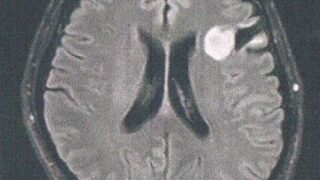

GLIOMA:手術後132ヶ月目の検査

手術から11年が経過した。半年ごとの定期検査です。検査概要びまん性星細胞腫グレード2(悪性転化しやすい腫瘍)MRI検査: 造影剤なし / 造影剤あり造影剤ありの場合:4時間前から絶食し、MRIの1時間前に血液検査を済ませる。診断結果着実に大...